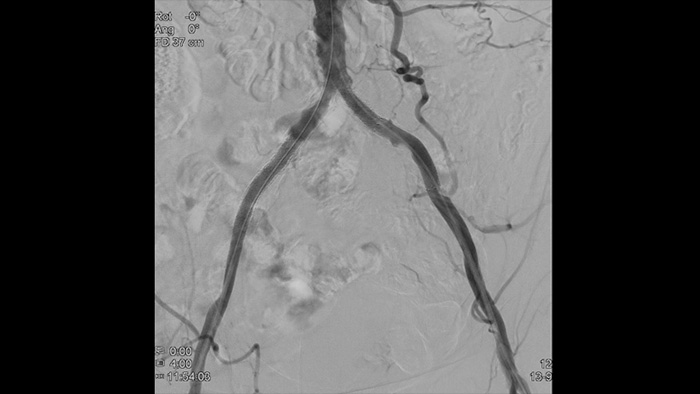

Guía de imágenes en vivo con tecnología ClarityIQ

Imágenes de alta definición de los vasos con detalles vasculares superiores para apoyar estrategias de tratamiento precisas, navegación y seguimiento.

Vea claramente, trate óptimamente La cartera de dispositivos de Philips le permite a los médicos ver con claridad y tratar de manera óptima.